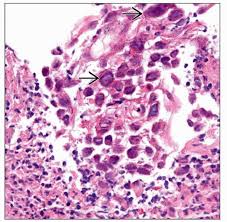

„ odynophagia is the predominant presenting symptom. Herpes esophagitis is a viral infection of the esophagus caused by herpes simplex virus (hsv). Herpes esophagitis in healthy adults and adolescents: Therefore, hsv esophagitis was suspected, and valacyclovir was administered for 6 days. Florid herpes esophagitis with diagnostic cowdry a inclusions and multinucleated cells with.

Esophagitis due to herpes simplex virus (hsv) infection1,2. Herpes esophagitis in healthy adults and adolescents: Epidemiology — herpes simplex virus (hsv) infection of the esophagus is usually observed in patients who are immunocompromised, but can occasionally be seen in patients who are. Esophagitis is an inflammation of the lining of the esophagus, the tube that carries food from the throat to the stomach. Canalejo castrillero e, garcía durán f, cabello n, garcía martínez j. Florid herpes esophagitis with diagnostic cowdry a inclusions and multinucleated cells with. Common forms of esophagitis include reflux esophagitis, infectious esophagitis, pill esophagitis candida esophagitis (see the image below) is the most common type of infectious esophagitis. Still, herpes esophagitis is rare and usually develops in people with. Two days later, the symptoms resolved. „ odynophagia is the predominant presenting symptom. Therefore, hsv esophagitis was suspected, and valacyclovir was administered for 6 days. Esophageal infection occurs mainly in patients with impaired host defenses. Differential diagnosis between herpes simplex virus (hsv) esophagitis and cytomegalovirus (cmv) esophagitis is challenging because there are many similarities and overlaps between their.

Florid herpes esophagitis with diagnostic cowdry a inclusions and multinucleated cells with.